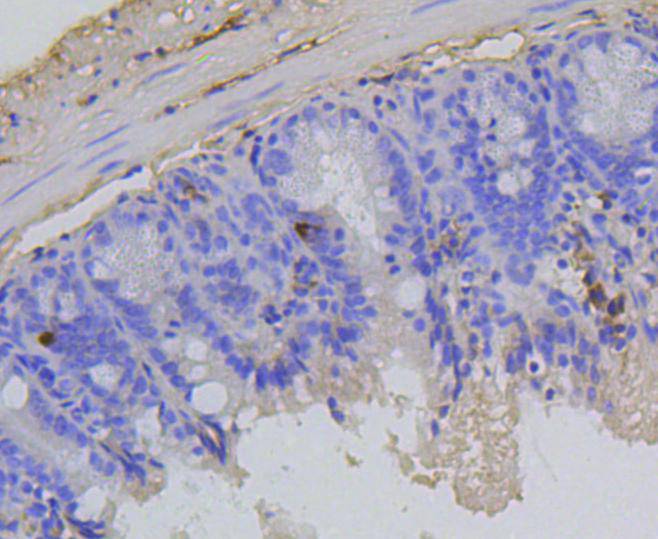

Immunohistochemical analysis of paraffin-embedded mouse spleen tissue using anti-Phospho-Rb(S807) antibody. Counter stained with hematoxylin.

Immunohistochemical analysis of paraffin-embedded human tonsil tissue using anti-Phospho-Rb(S807) antibody. Counter stained with hematoxylin.

Immunohistochemical analysis of paraffin-embedded human colon cancer tissue using anti-Phospho-Rb(S807) antibody. Counter stained with hematoxylin.

Immunohistochemical analysis of paraffin-embedded human spleen tissue using anti-Phospho-Rb(S807) antibody. Counter stained with hematoxylin.

Immunohistochemical analysis of paraffin-embedded human breast carcinoma tissue using anti-Phospho-Rb(S807) antibody. Counter stained with hematoxylin.

Immunohistochemical analysis of paraffin-embedded mouse colon tissue using anti-Phospho-Rb(S807) antibody. Counter stained with hematoxylin.